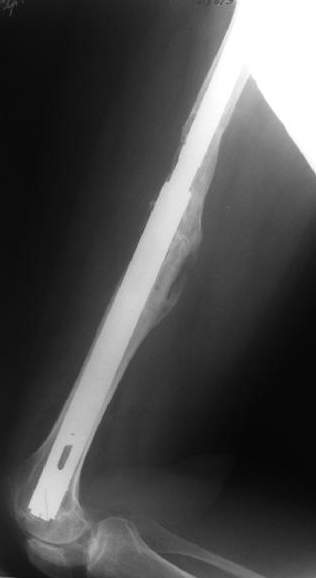

Female, rheumatoid, THA in 2003, car accident in 2006, failed plating. Nailing in Oct 2007. The nail is solid with hollow proximal part where the stem is docked. Last images are in 1 year after

nailing.

The femur responded by failure to Mennen plating (DePuy Bridge plate). So i would add that the ability to unite is realized in mechanically and biologically sound conditions.